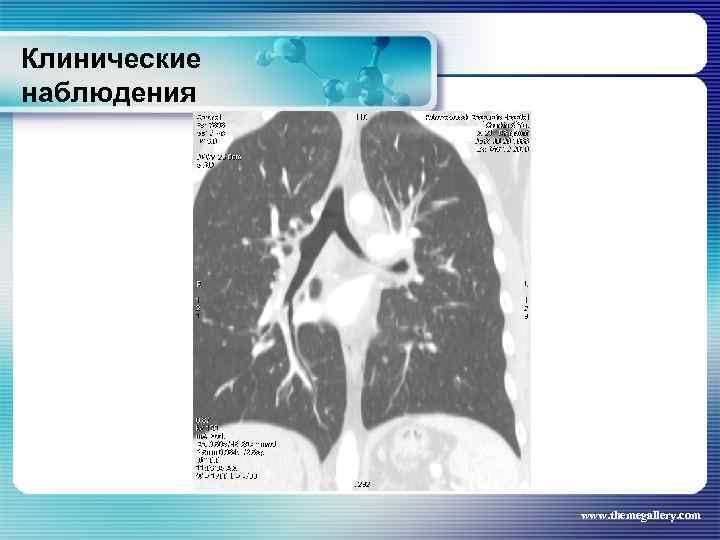

Клинические наблюдения Тот же пациент На основании выполненных исследований сформулирован клинический диагноз: лимфома Ходжкина, нодулярный склероз Grade II, III A E S стадия с поражением шейных, заднешейных, надключичных лимфатических узлов, средостения с прорастанием в левое легкое и плевру слева, внутригрудных лимфатических узлов, абдоминальных лимфатических узлов, селезенки. За время наблюдения проведено 8 циклов BEACOPP. На этом фоне достигнута в марте 2010 года парциальная ремиссия. При лучевом обследовании выявлена положительная динамика изменений. www. themegallery. com

Клинические наблюдения Тот же пациент На основании выполненных исследований сформулирован клинический диагноз: лимфома Ходжкина, нодулярный склероз Grade II, III A E S стадия с поражением шейных, заднешейных, надключичных лимфатических узлов, средостения с прорастанием в левое легкое и плевру слева, внутригрудных лимфатических узлов, абдоминальных лимфатических узлов, селезенки. За время наблюдения проведено 8 циклов BEACOPP. На этом фоне достигнута в марте 2010 года парциальная ремиссия. При лучевом обследовании выявлена положительная динамика изменений. www. themegallery. com